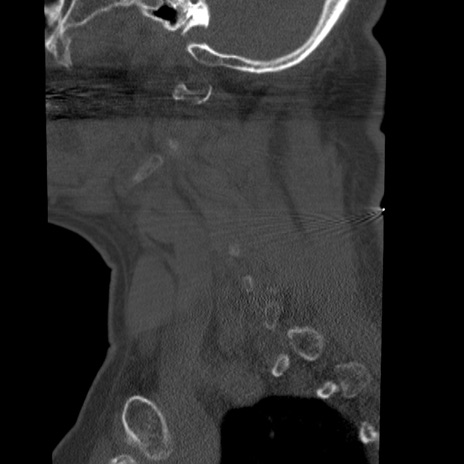

症例50 頚椎CT(矢状断像)

【症例】60歳代女性

【主訴】後頭部〜右後頸部にかけての痛み

【現病歴】本日飲食店でコーヒーを飲んでいたところ、突然後頭部〜右後頸部にかけて痛みが出現し、右上肢の感覚障害を伴ったため救急要請。

【身体所見】脳神経学的に明らかな異常所見を認めず。右上肢に軽度の感覚障害あり。

異常所見と診断は?

横断像

冠状断像